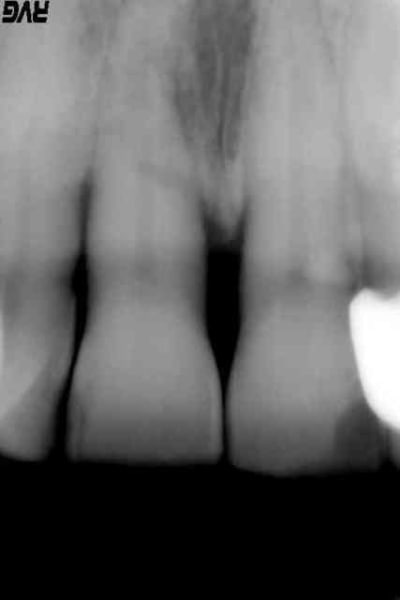

patiente 45 ans, pas de pb médicaux particulier, hygiène presque correcte, se présente ce matin au cabinet pour mobilité de 11 avec sensibilité au froid et au chaud depuis 10 jours.

Examen clinique : mobilité de 11 marquée, sensibilité à la mobilisation, hypersensibilité au froid. Leger trauma occlusal, pas de choc récent sur la dent.

Examen radio : voir PJ, on dirait outre un pb paro évident, une fracture de la racine au niveau de l'os alvéolaire mais pourquoi? L'endodonte semble bizarre au delà de l'os...